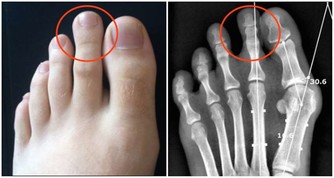

在爬山和爬樓梯的時候,膝關節會承受超過本身體重3到4倍的壓力。

尤其是50歲以後,人的膝關節多少都會有些磨損的情況,此時,就要減少此類運動。

對於有些有過膝關節損傷的朋友40歲以後就要特別注意了。